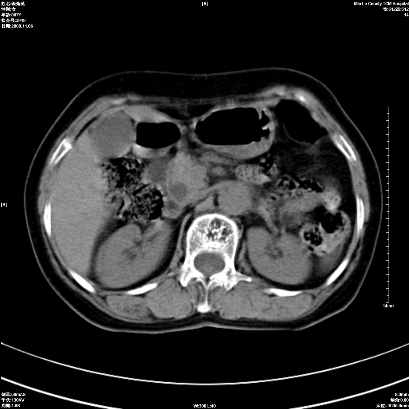

以下是引用卜一在2008-11-6 15:58:00的发言:[br]胰头略增大,胆总管扩张,末端渐行性狭窄。多考虑:胰头癌!建议增强!